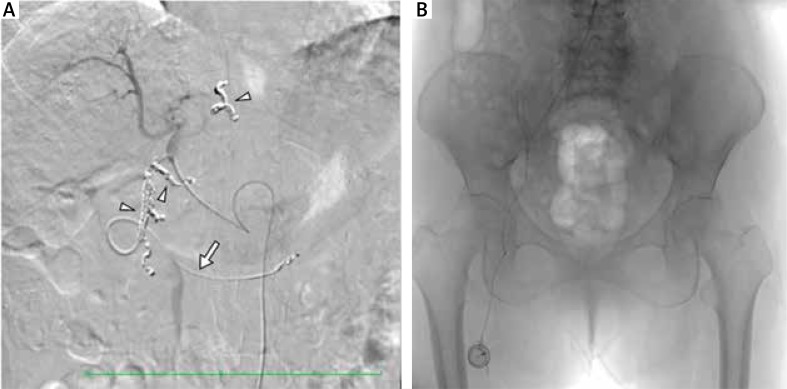

Eighty-five patients (86.7%) started sorafenib at a reduced dosage of 400 mg/day according to their age, body weight, and co-morbidities, at the physician’s discretion. If the starting dose was tolerated, it was increased stepwise to 600 or 800 mg/day. In the combination group, sorafenib was administered for 1–2 months based on tolerability, after which HAIC was performed sequentially. Briefly, on day 1 of HAIC, 50 mg of cisplatin in 5–10 ml of lipiodol was injected through a subcutaneously implanted port system (Fig. 1) with adequate systemic hydration. Then 5fluorouracil (5-FU) (250 mg/day) was continuously infused using a syringe pump for 10 days (on days 1–5 and 8–12) with two days off treatment. This sequential sorafenib-HAIC regimen was repeated every 2–3 months (Fig. 2). The interval between sorafenib treatment and HAIC was not specified but did not exceed two weeks. We reduced the dose of cisplatin by 25–50% in patients with pre-existing or new-onset renal insufficiency, but the dose of 5-FU was fixed in principle. Dose reduction or interruption of sorafenib in response to toxicity was performed in all subjects according to the general recommendations. If the tumour became refractory or there was intolerance to combination therapy or sorafenib monotherapy, patients were considered for subsequent therapy providing that survival or quality of life benefit was expected. Tumour response and disease progression were evaluated by using the modified Response Evaluation Criteria in Solid Tumours criteria [20], and adverse effects were graded according to Common Terminology Criteria for Adverse Events (version 4.03).

Fig. 1.

Placement of a port-catheter system for hepatic arterial infusion chemotherapy. A) The tip of the intra-arterial catheter with a side hole was inserted into the gastroduodenal artery (GDA) (arrow), and the side hole was located at the common hepatic artery. The GDA and other arteries supplying the gastroduodenal region were embolised using metallic coils (arrowheads) to prevent gastroduodenal mucosal damage by chemotherapy agents. B) The other end of the catheter was connected to the injection port, which was implanted in a subcutaneous pocket at the proximal anterior thigh